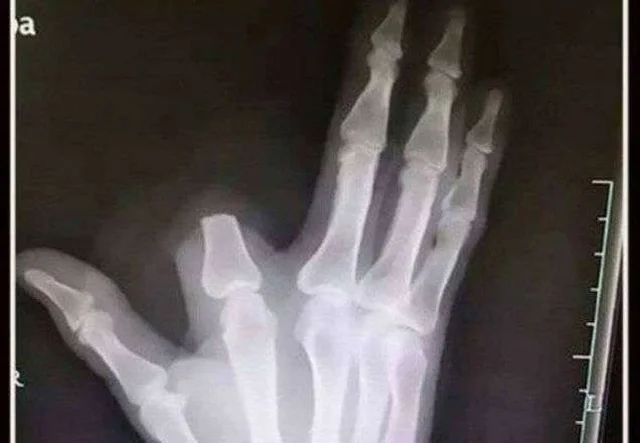

Homem corta o próprio dedo para conter veneno de cobra e descobre que ela nem era venenosa/Foto: Reprodução

Tomado pelo desespero, Zhang decidiu amputar o dedo para conter o suposto avanço do veneno. Em seguida, percorreu cerca de 80 quilômetros até o hospital mais próximo, onde recebeu a surpreendente notícia: a cobra não era venenosa.

Segundo os médicos, o animal identificado era uma Deinagkistrodon, espécie comum na região, mas sem veneno letal. O gesto heroico, e precipitado, acabou resultando em um dano permanente.

Para piorar, o idoso deixou o dedo amputado no local da picada, o que impossibilitou qualquer tentativa de reimplante. “Se ele tivesse trazido o membro, poderíamos ter realizado uma cirurgia de reimplantação com boas chances de sucesso”, explicou um dos cirurgiões.